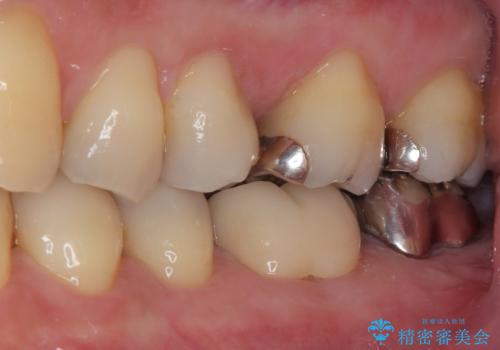

- 奥の銀歯が外れしまったとのことで来院された患者様です。

非常に咬合力が強く、銀歯の周りの歯がむし歯になっている状態でした。

部分的な詰め物ですと、再度周辺がむし歯になるリスクが高いと考えられたため、オールセラミッククラウンにて補綴治療を行うこととしました。